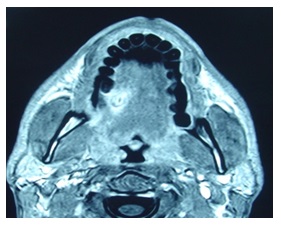

A thirty-year-old male without any previous medical history came to the accident and emergency department, at the General Hospital of the main city of this area. He complained of mouth pain. There was a large tuna fish bone on the mid right dorsal border of the tongue, which was removed. A few days later, he represented with a painful swelling of the tongue. A glossal abscess was aspirated with a large bore needle. An oral wide spectrum antibiotic and a non-steroidal anti inflammatory drug were prescribed. Two weeks later he returned with an increased tongue swelling without compromising the airway which showed a deep lesion in the lingual muscle (Figure 1&2) to the left of the midline Under general anaesthesia a wide incision of the lesion on the ventral tongue the direction of Wharton’s and further dissection of the former abscess opening. A silicone drain was left in place and the incision closed by three stitches. The patient improved a few hours after, and the episode resolved completely without any further complications (Figure 3&4).

Figure 2

Figure 2: More posterior imagine of the lesion.